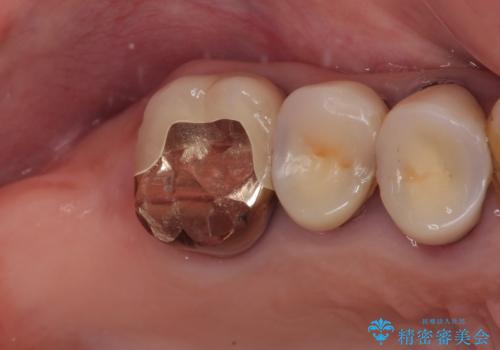

- 食事が取れないほどの激痛で、インプラント治療を希望して来院された患者様です。

近医にてクラウンを除去してもらった状態での来院でした。

遠心が歯根破折しており、歯槽骨が著しく吸収している状態であったため、抜歯即時でのインプラント埋入は断念し、2ヶ月ほど待機してから埋入することとしました。